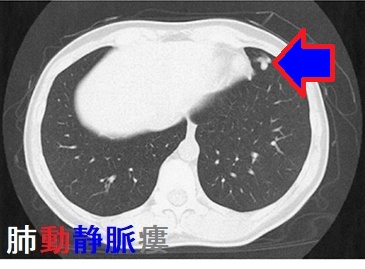

甲状腺乳頭癌 肺転移 CT画像。中-下肺野に、小粒状陰影が多数あります。

甲状腺癌の肺転移様式として、両側肺に、びまん性多発小結節を形成するのが普通です(上記肺X-p、CT画像)。孤立結節型は11.4%とされます。